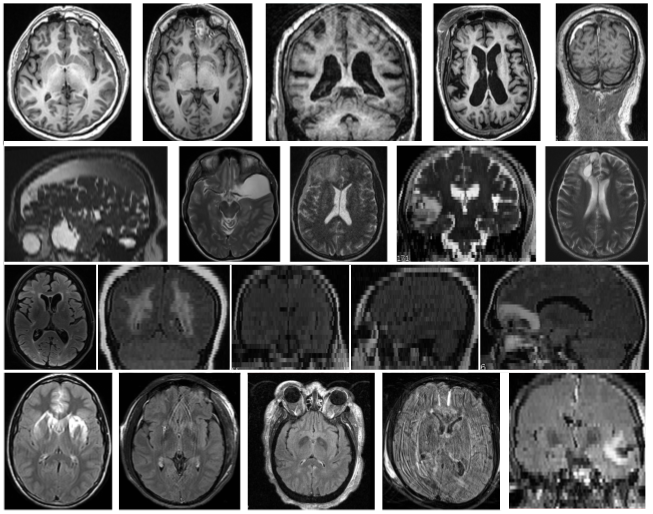

Refer to caption

Figure 1: Each row shows examples of pre-contrast T1subscript𝑇1T_{1}, T2subscript𝑇2T_{2}, pre and post-contrast FLAIR images, respectively, from our test dataset. Note the heterogeneity among brains regarding anatomy, disease type, resolution, field of view, and imaging artifacts such as noise, motion, ghosting, and intensity heterogeneity.

In this paper, we propose a new CNN architecture called PhiNet (ΦΦ\Phi-Net), which borrows the powerful skip connection concept from the deep residual network ResNet [13]. ΦΦ\Phi-Net was designed with the specific purpose of classifying different contrasts of MR images while being robust to different types of pathologies, such as Alzheimer’s disease, multiple sclerosis, and traumatic brain injury. Example images from our training and test dataset are shown in Fig. 1. Although there are numerous other MR contrasts, we chose these broad categories because these image types are the ones most widely used in various clinical image processing algorithms such as tissue segmentation and registration.